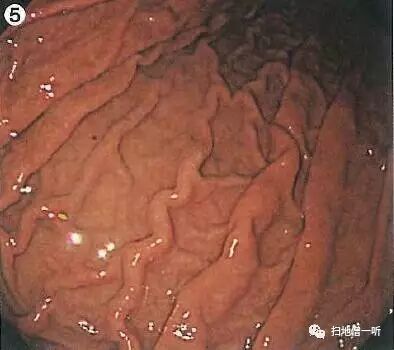

胃体部粘膜整体RAC可见,背景粘膜光滑,提示HP未感染。在HP未感染背景下应警惕印戒细胞癌的发生。胃体下部小弯侧可见小片状褪色粘膜,注意观察此处。

胃窦部水肿伴多发糜烂,呈串珠样改变,隆起糜烂处以外的背景粘膜未见明显水肿变化。此种表现在“京都胃炎分类”中以“隆起型糜烂”称之,多提示HP未感染。